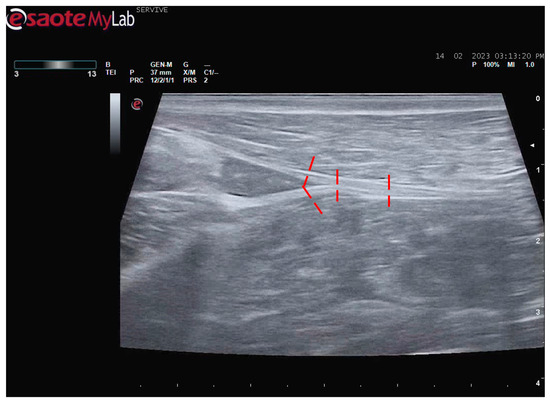

Figure 6.

Schematic representation of the measurement sites for the diameter of the sciatic, common peroneal, and tibial nerves. The measurement sites are identified by the red dashed lines.